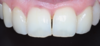

Le sourire est naturel et plus présent Les diastèmes sont refermés par 2 facettes céramique sur les incisives latérales et une stratification de composite sur la canine gauche

Le sourire est naturel et plus présent, diastèmes refermés par 2 facettes et composite. Cas clinique 4 : facettes latérales.